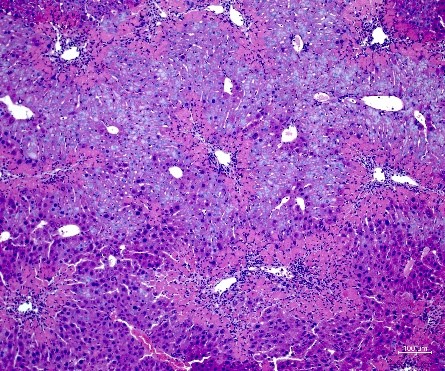

Our group was committed to supporting the GRAFT trial (Granulocyte-colony stimulating factor (G-CSF) to treat acute-on-chronic liver failure: A multicenter randomized trial) with translational research, with experiments continuing far beyond the end of the trial. Blood from study patients was tested and sent to our laboratory for further analysis. The overall aim was to evaluate the clinical relevance of cellular and non-cellular immune responses in acute-on-chronic liver failure (ACLF). Clinical evaluations were complemented by experiments in the mouse model and in vitro. We focus on the importance of purinergic DAMPS and ectonucleotidases, such as CD39, in regulating innate immune responses and modulating exacerbated inflammation in ACLF.